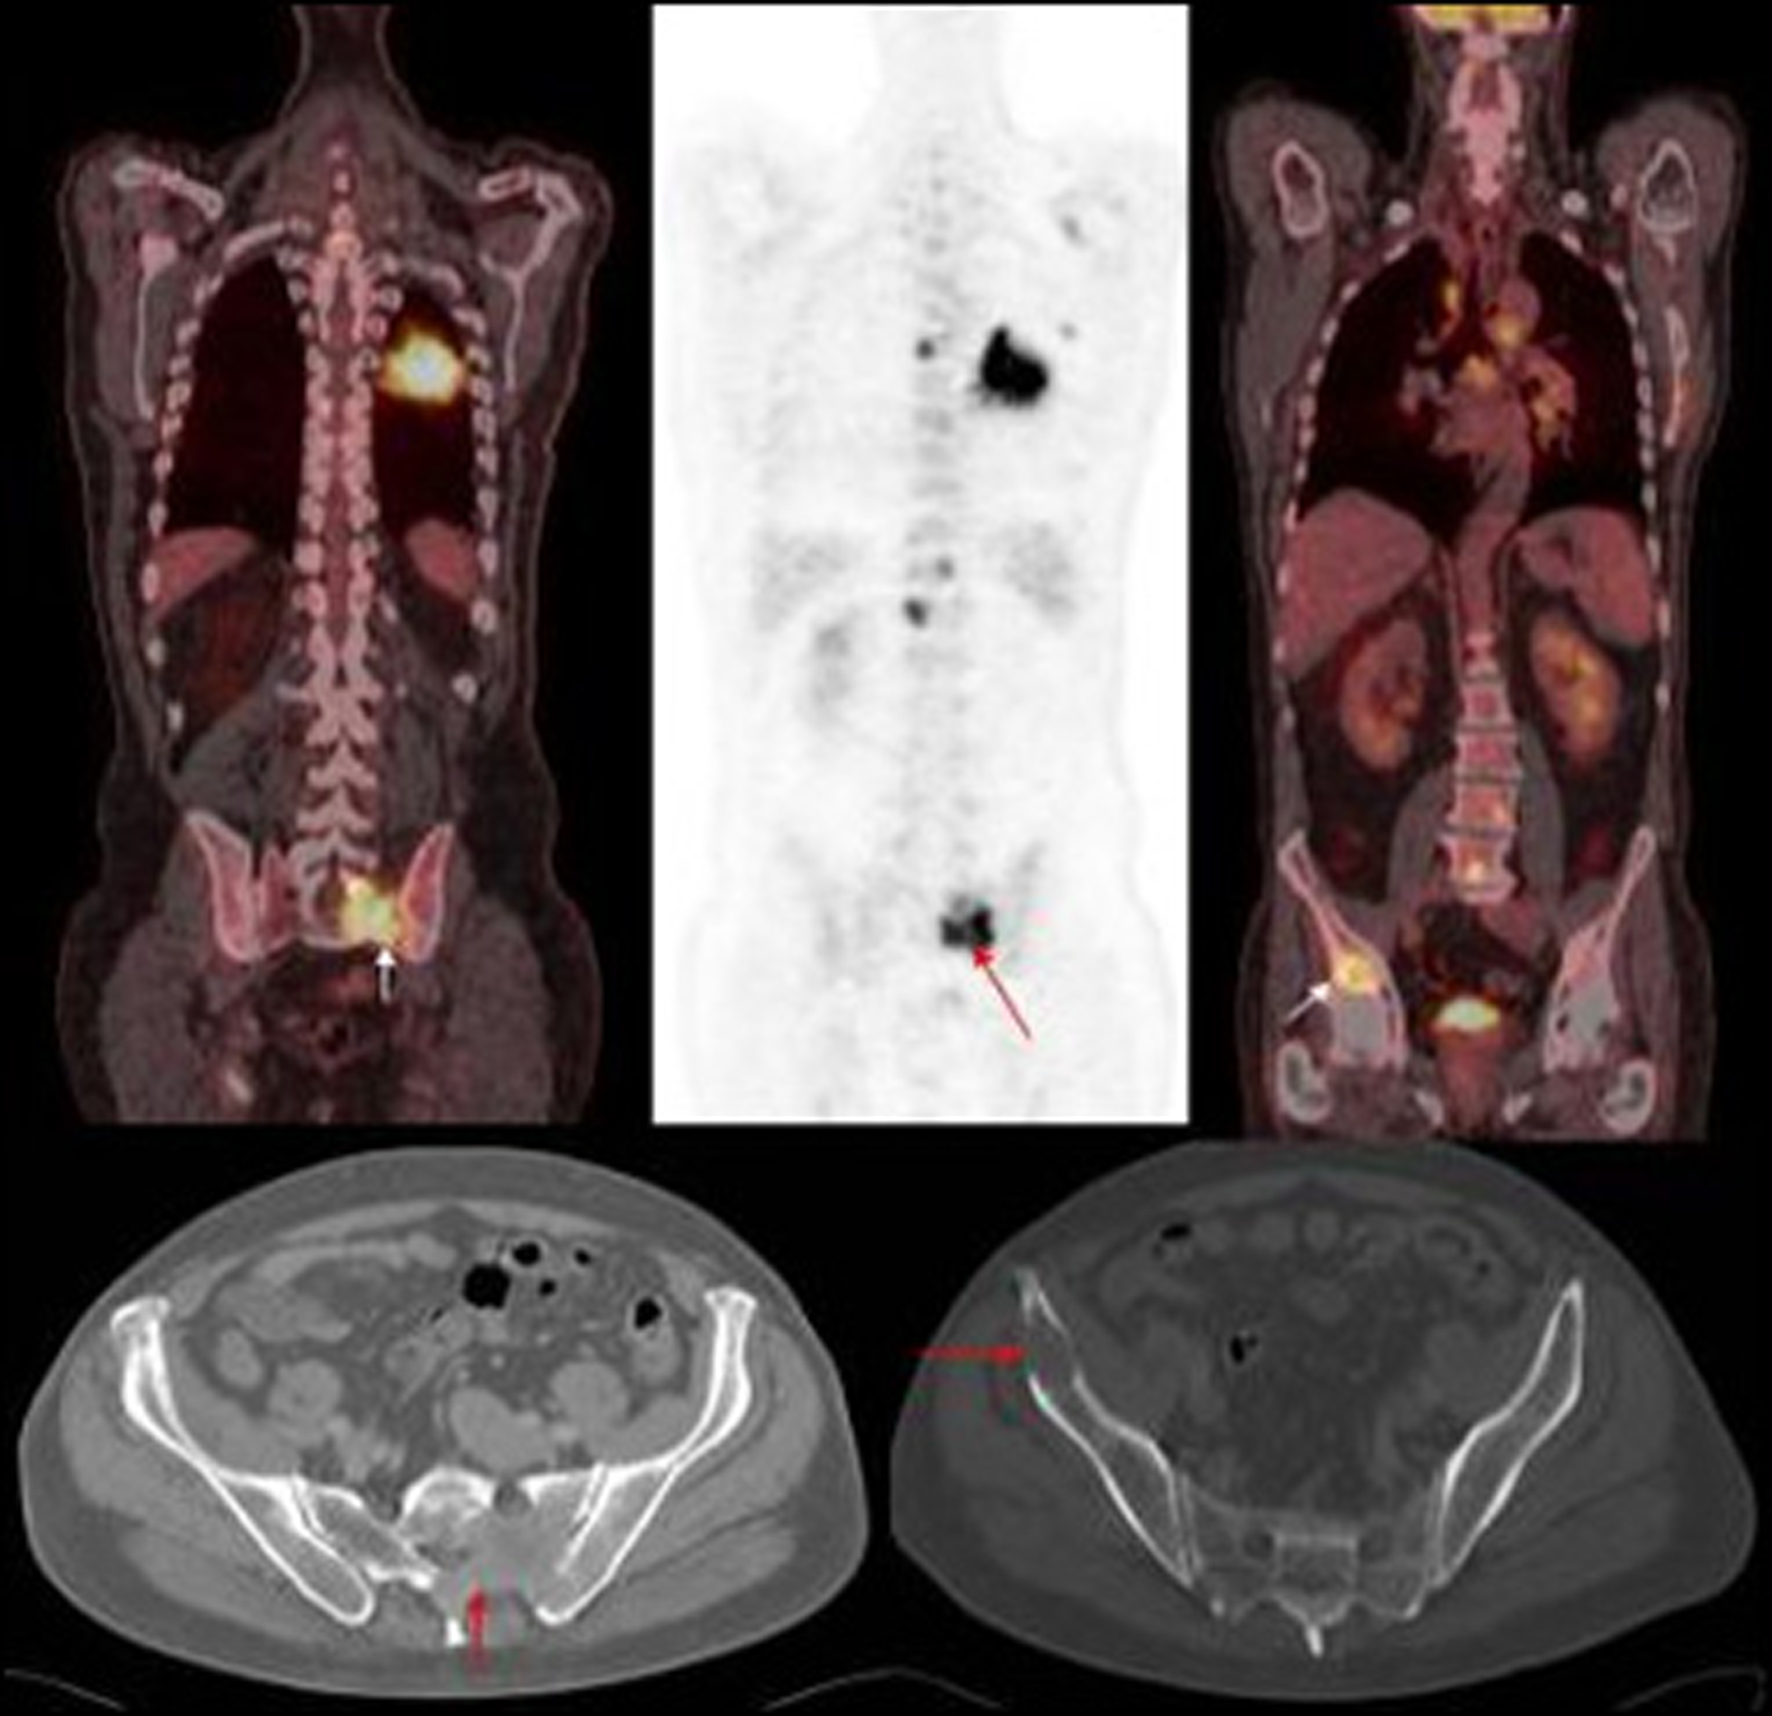

In our study nearly half of the in field metastasis were identified by two observers (Fig. 1). Most of the missed in field metastasis were bony involving the ribs, acromion and spine (Fig. 2, 3, 4). This could be explained by a number of reasons. Firstly it is easier to overlook a small bony metastasis especially in the ribs. Secondly, MIP (maximum intensity projection) reconstructions helps to depict the metastatic deposits better. If one does not routinely perform these, it might account for the missed deposits.

![]() Click for large image | Figure 1. PET images of primary left lung cancer metastatic deposits in the bony pelvis and lumbar vertebrae with corresponding axial CT images of the pelvis. |